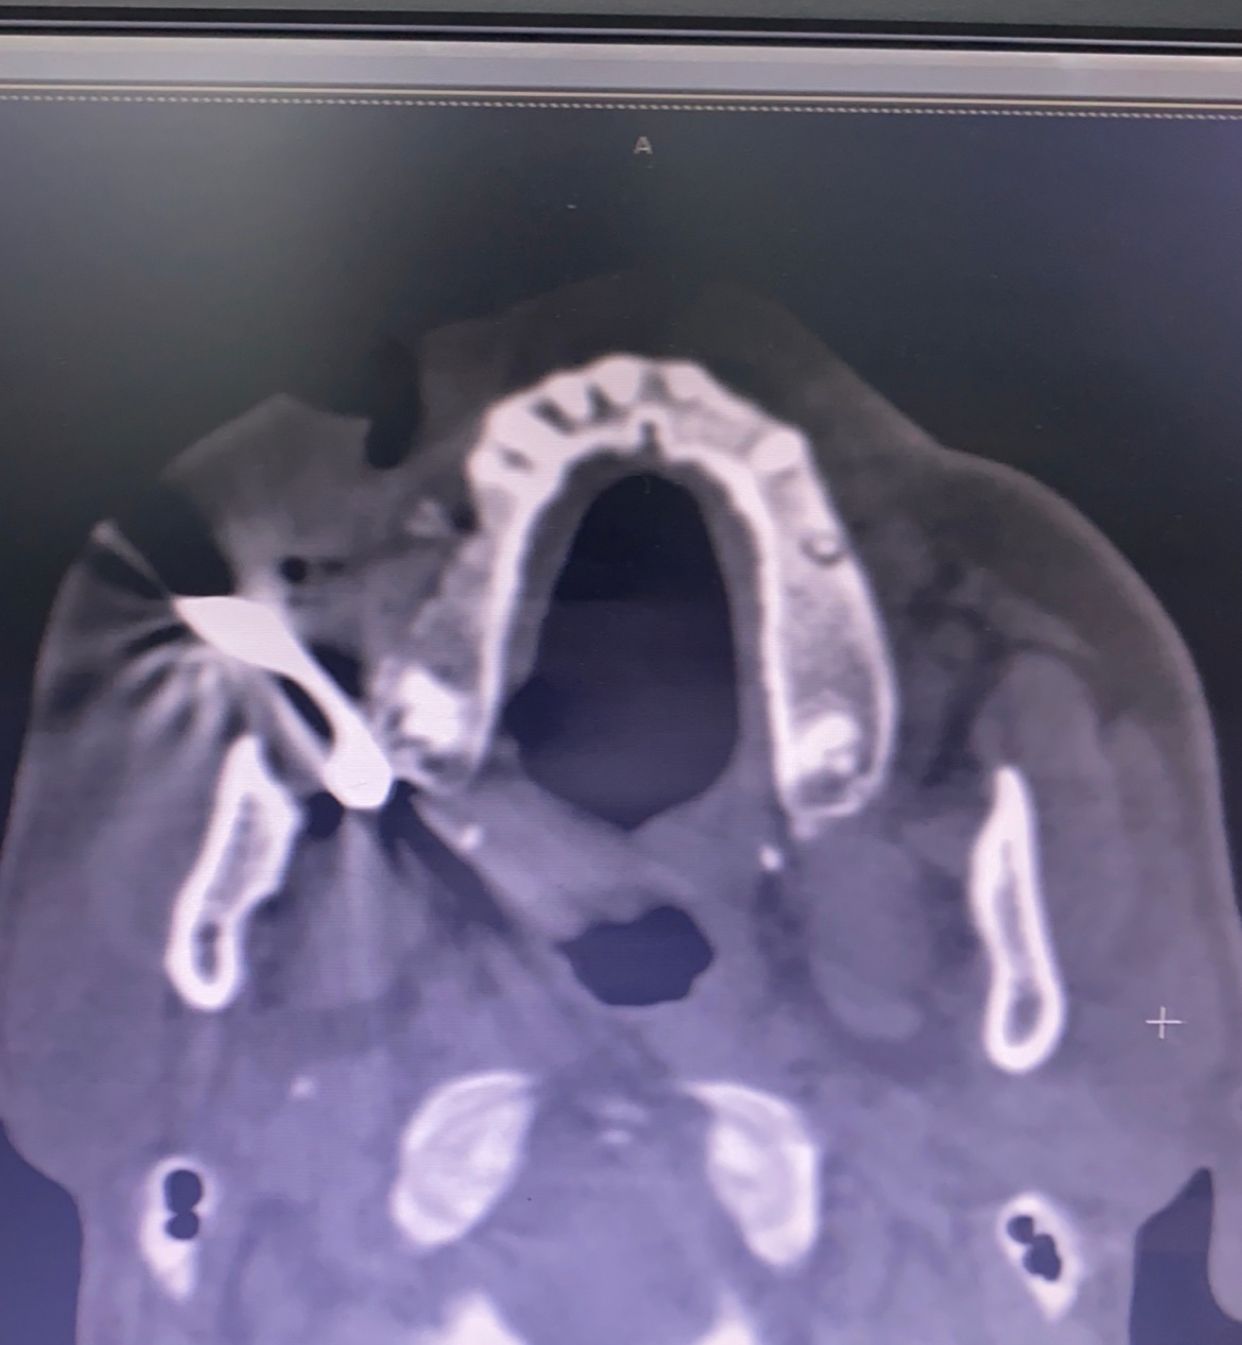

تمكن فريق طبي بقسم جراحة الوجه والفكين بمستشفى أبها الخاص العالمي بعسير ، من إجراء عملية جراحية لإنقاذ مقيم بالعقد الرابع من العمر بعد إصابته في الوجه أثناء عمله بمهنة الحدادة مما أدى إلى شقوق عميقة بأنسجة الخد والشفة ونزيف حاد بالأوعية نتيجة دخول اجسام معدنية .

في هذا الإطار أوضح الدكتور فؤاد العُمري استشاري جراحة الوجه والفكين أنه تم إجراء عملية ايقاف نزيف الاوعية الدموية، وإزالة الاجسام المعدنية والمسامير بالوجه ،وإغلاق الجروح تجميلياً دون أي مضاعفات ولله الحمد ، مضيفاً : اُجريت الجراحة من خلال الفريق الطبي برئاستي ، بالإضافة إلى الدكتورة هند عبدالناصر اخصائية التخدير بالمستشفى، ولقد تمت متابعة استشفاء المريض وينعم بصحة وعافية.